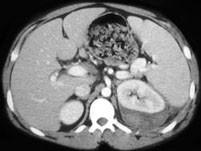

问题 男,35岁,左侧腰部胀痛,有外伤史,请根据所示图像,选择最可能诊断 ( )

选项 A、左肾盂输尿管连接处撕裂 B、左肾动脉撕裂 C、左肾包膜下血肿 D、左肾碎裂 E、左肾挫伤

答案 E